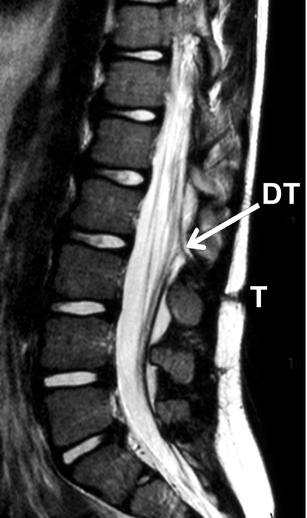

At MR imaging, the conus was estimated at L1–L2. At L2–L3 level, a tenting of the dura was seen, presumably continuing as a trajectory up to the skin defect (Fig. 4).

Fig. 4

figure 4

Sagittal T2-weighted MR image showing the subcutaneous trajectory (T) as well as the tenting of the dural sac (DT)

In two cases, dorsal tenting of the dura was found. In case 1, this was noted peroperatively as in case 2 it was clearly shown by MR imaging. Histological examination of the resected tract in case 2 showed tissue with dural origin. This was previously described by Scotti et al., who reported on a case of a thoracic DS with dorsal tenting of the dura. Although histological examination of this tract revealed an epidermal-lined tract, it was mainly composed of dense collagenous tissue with foci of meningeal tissue [15].

In the three cases described in this report, MR imaging vaguely demonstrated the trajectory of the stalk. However, the connection of the stalk with the spinal cord was not demonstrated in any case. No empyema or dermoid mass were seen, whereas these are common findings in case of a typical DS [3, 4, 17]. In case 2, dorsal tenting of the dura was clearly demonstrated.